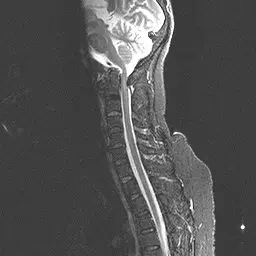

44.下圖為何種 MR 影像?

AA.coronal T1 weighted MR

BB.axial T2 weighted MR

CC.sagittal T1 weighted MR

DD.sagittal T2 weighted MR

- 解剖切面分析:觀察圖片,我們可以看到頸椎(Cervical spine)的椎體(Vertebral bodies)由上而下排列,並能清楚看見後方的腦幹、小腦以及向下延伸的脊髓(Spinal cord)。這種將人體分為左右兩半、呈現側面輪廓的切面,即為矢狀面(Sagittal plane)。

- 影像權重分析:接著觀察組織的訊號特徵。最明顯的指標是包圍在脊髓外圍的腦脊髓液(Cerebrospinal fluid, CSF)。在圖中,脊髓腔內的 CSF 呈現非常明亮的高訊號(Hyperintense,白色)。相對地,脊髓實質本身呈現較暗的灰色(中等訊號)。此外,健康的椎